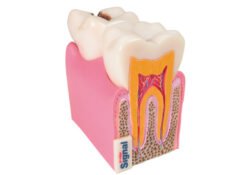

Modelo anatómico dentadura

Peana muela